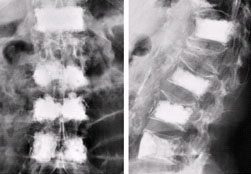

脊柱骨折

應(yīng)由3~4人在同一側(cè)同時(shí)托住傷員的頭、肩、臀和下肢,把傷員平托起來,平臥在木板上,并用繃帶加以固定。傷者最好取俯臥位,并在胸腹部放一軟枕。嚴(yán)禁采用“搬頭搬腳”的抬抱方式移動(dòng)或搬運(yùn)傷者,也禁用普通的軟擔(dān)架搬運(yùn)。